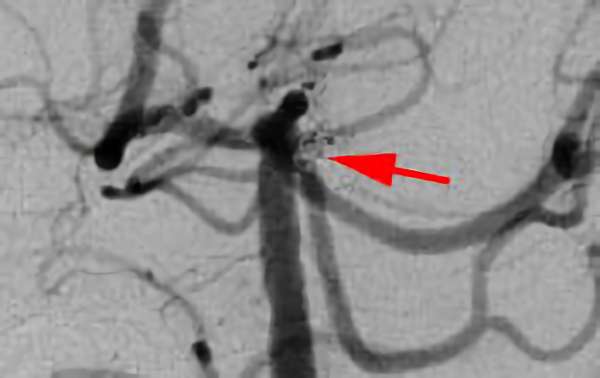

'18年3月

脳底動脈瘤

50代

院内外来

No.83 手術前

No.83 手術中

No.83 手術後